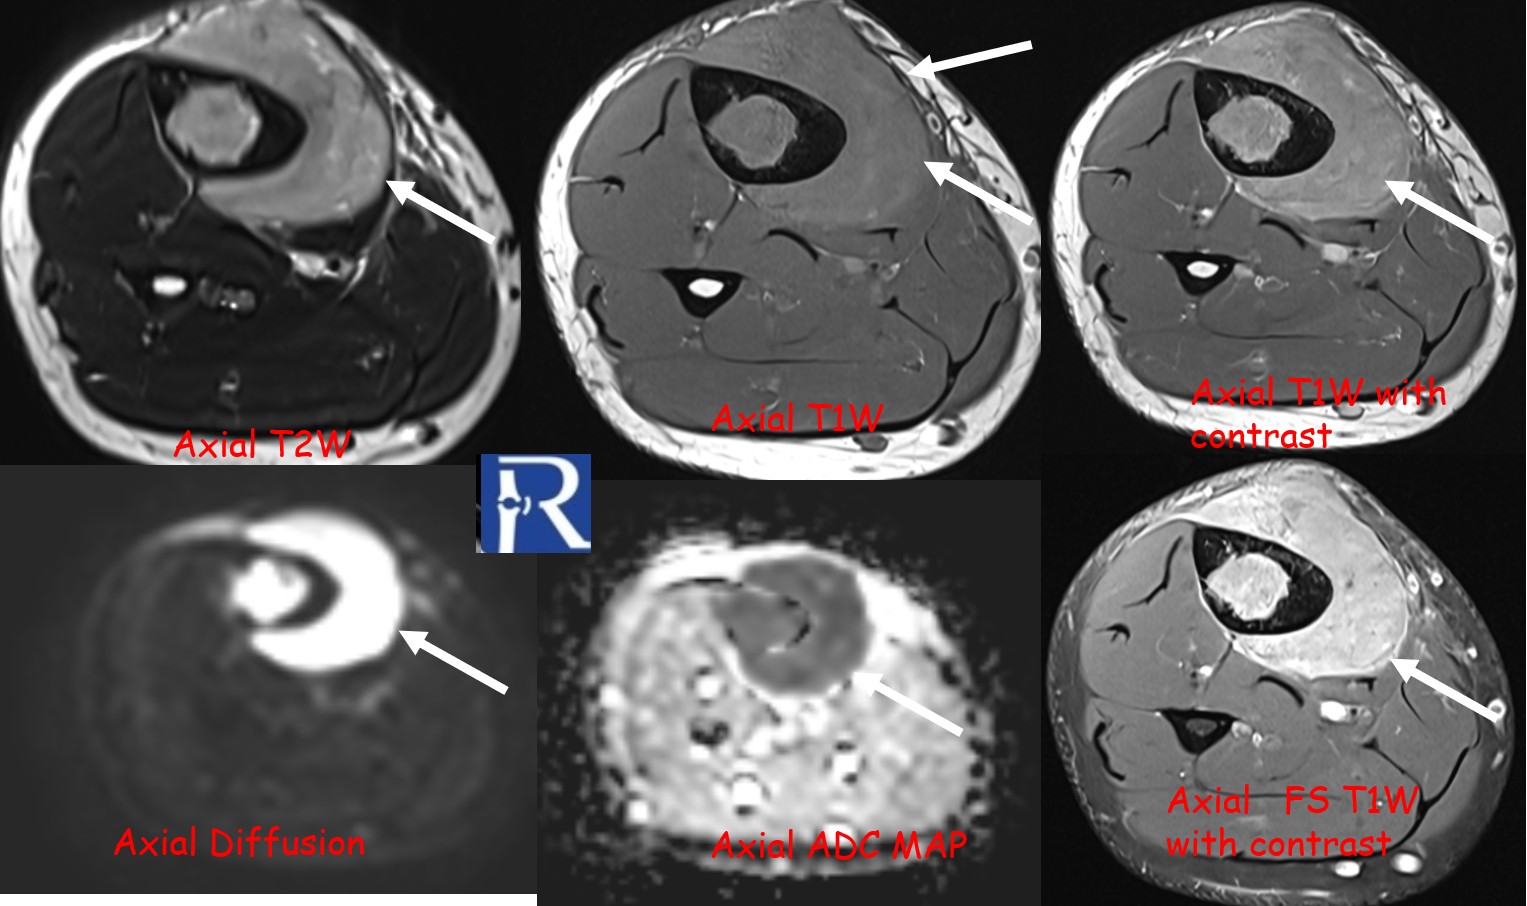

MRI revealed a significant soft-tissue component extending beyond the cortical margin, appearing hypointense on T1-weighted and intermediate on T2-weighted sequences, with heterogeneous contrast enhancement.

Diffusion-weighted imaging (DWI) showed marked diffusion restriction in both osseous and soft-tissue components, reflecting high cellularity.

These imaging findings—particularly the absence of periosteal reaction, intermediate T2 signal, and marked DWI restriction—favored the diagnosis of lymphoma over Ewing sarcoma.